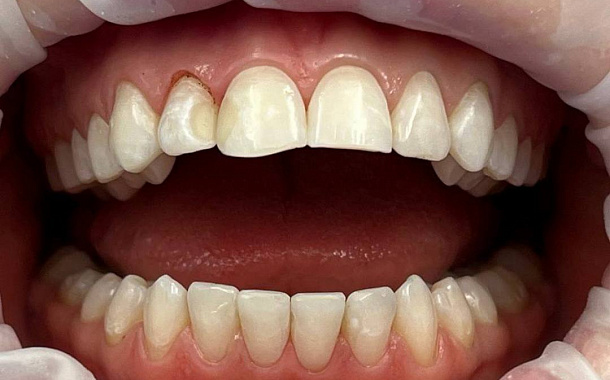

Для решения эстетических проблем передних зубов устанавливаются керамические накладки, или, по-другому, виниры. Они подбираются таким образом, чтобы придать зубам естественную белоснежность и красивую, ровную форму.

Установленные виниры совершенно не отличить от настоящих зубов, при этом они позволяют скрыть различного рода изъяны. Реставрацию зубов винирами используют, когда нужно скрыть или скорректировать:

сколы и трещины на зубах

неправильную форму зубов

увеличенные промежутки, щели между зубами, диастема

лёгкую скученность зубов

Реставрация зубов винирами также улучшают эстетику лица. За несколько визитов в стоматологию вы получаете фактически новую улыбку — сияющую и эстетичную, как из глянцевого журнала.